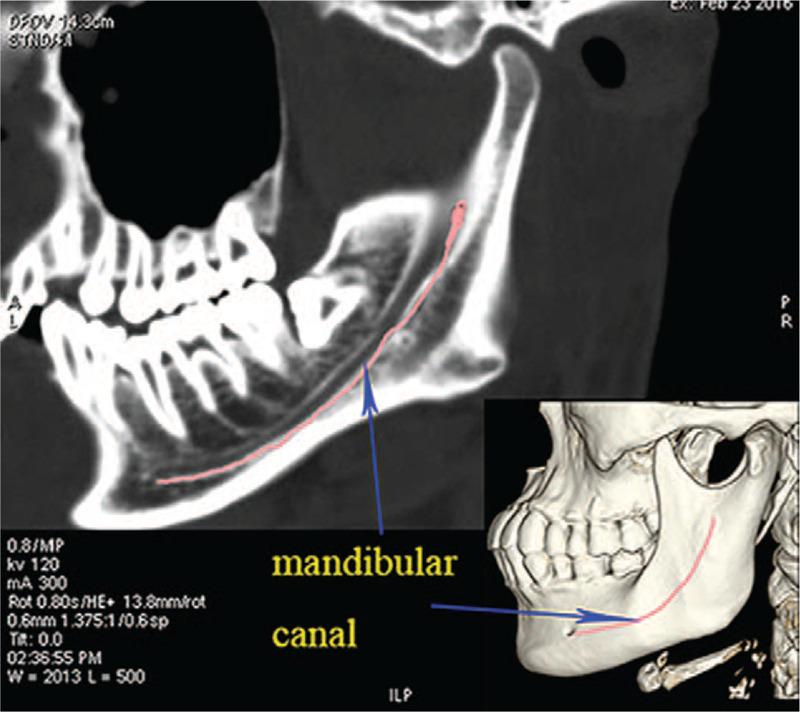

This study aimed to measure temporomandibular joint (TMJ) with 3-dimensional (3D) reconstruction technique in Chinese northeast population, and to clarify the region for fixation and to provide morphological basis for the application of TMJ prosthesis in Chinese setting.Computed tomography (CT) scan and 3D reconstruction were performed with 132 individuals. Structural markers and measurements were further performed with a 3D model of the total TMJ, including the width, thickness and angle of zygomatic arch, the width and height of articular fossa, as well as the area, width, thickness and angle of mandible in the fixation region of the TMJ prosthesis. All the measured indicators values were compared between bilateral sides and gender groups.There was no statistical difference in the measured indicators between the left side and the right side (P > .05). However, certain parameters, including S, L5, L7, P4, and P5, were significantly different among males and females (P < .05).In this study, 3D CT image was used to obtain the measurement data of TMJ, which provided data support for the clinical application of TMJ prosthesis in Chinese population.

本研究旨在采用三维(3D)重建技术对中国东北地区人群的颞下颌关节(TMJ)进行测量,明确固定区域,为TMJ假体在中国的应用提供形态学依据。对132名个体进行了计算机断层扫描(CT)及3D重建。利用TMJ整体的3D模型进一步进行结构标记和测量,包括颧弓的宽度、厚度和角度,关节窝的宽度和高度,以及TMJ假体固定区域下颌骨的面积、宽度、厚度和角度。对所有测量指标值在双侧及性别组之间进行比较。左侧与右侧之间的测量指标无统计学差异(P>0.05)。然而,包括S、L5、L7、P4和P5在内的某些参数在男性和女性之间存在显著差异(P<0.05)。本研究利用3D CT图像获取TMJ的测量数据,为TMJ假体在中国人群中的临床应用提供了数据支持。